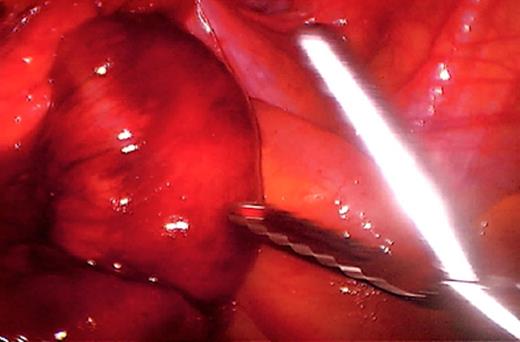

The initial management consisted of a NG tube insertion, IV hydration, and serial abdominal exams. Later, the patient was taken to the operating room due to the significant worsening of her pain. The abdomen was insufflated via the umbilicus with a Veress needle and a 5mm port was placed. Extensive adhesions were visualized throughout the pelvis which was carefully divided. The majority of the small bowel was normal in appearance (Fig. 3), but a segment of 1.5 feet was ischemic and surrounded by dense adhesions (Fig. 4).